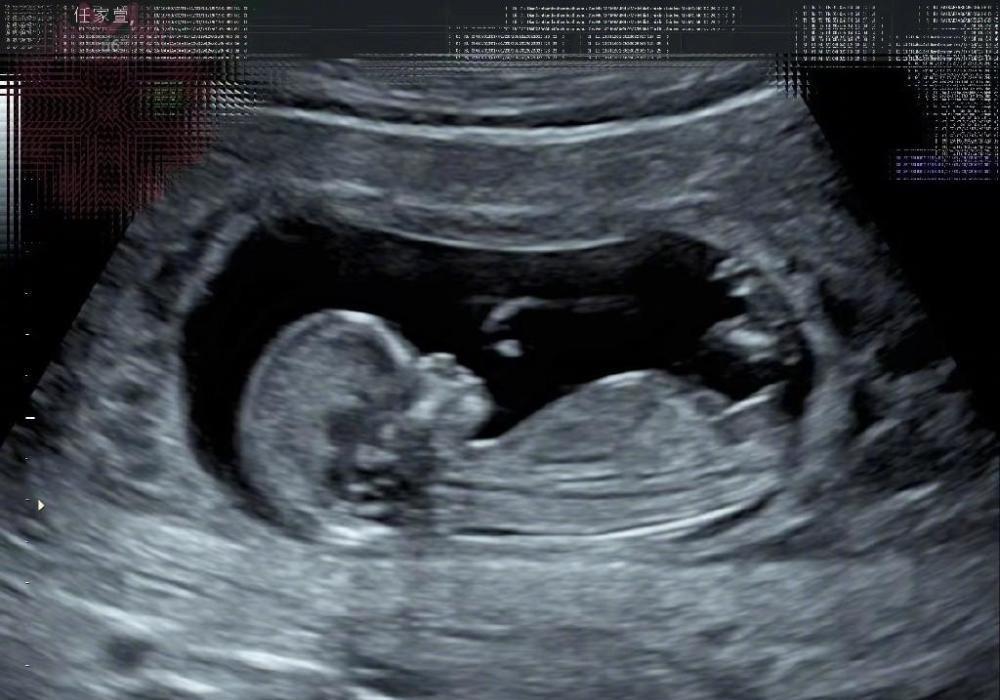

3月13日 , Selina在录制一档电台节目时 , 突然对外公布:“我任家萱怀孕了” 。 紧接着 , 就听到现场响起了一片热烈的掌声 。

另外 , 任家萱还表示 , 自己与丈夫已经给宝宝起好了乳名 , 不管是男孩还是女孩 , 都叫他(她)小腰果 , 至于为何取这样一个名字 , 任家萱也做出了解释 , 她表示 , 自己与丈夫去年曾去过一趟越南 , 令自己印象最深的就是当地种满了腰果 , 随后便检测出自己怀上了身孕 , 或许这就是所谓的缘分 。

由此推断 , 任家萱目前的孕肚应该十分明显 , 想必离预产期也越来越近了 , 由于实在掩藏不住内心的喜悦 , 这才通过电台向粉丝们告知 。